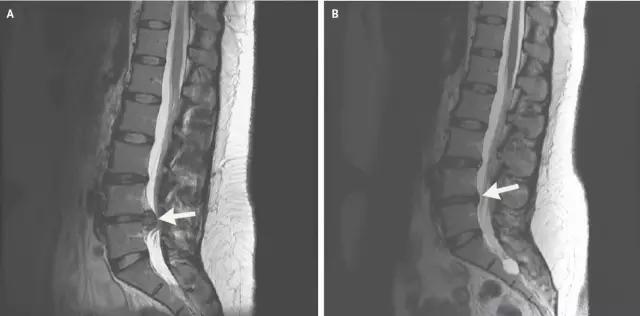

腰椎间盘突出症是纤维环破裂后髓核突出压迫神经根造成以腰腿痛为主要表现的疾病。腰间盘相当于一个微动关节,是由透明软骨板、纤维环和髓核组成,分布在腰椎骨间,腰椎间盘退行性改变或外伤所致纤维环破裂,髓核从破裂处脱出,压迫腰椎神经,从而出现腰腿放射性疼痛。腰椎间盘突出症以腰4-5、腰5-骶1发病率最高,约占95%,患者最多见的症状为疼痛,可表现为腰背痛、坐骨神经痛等。